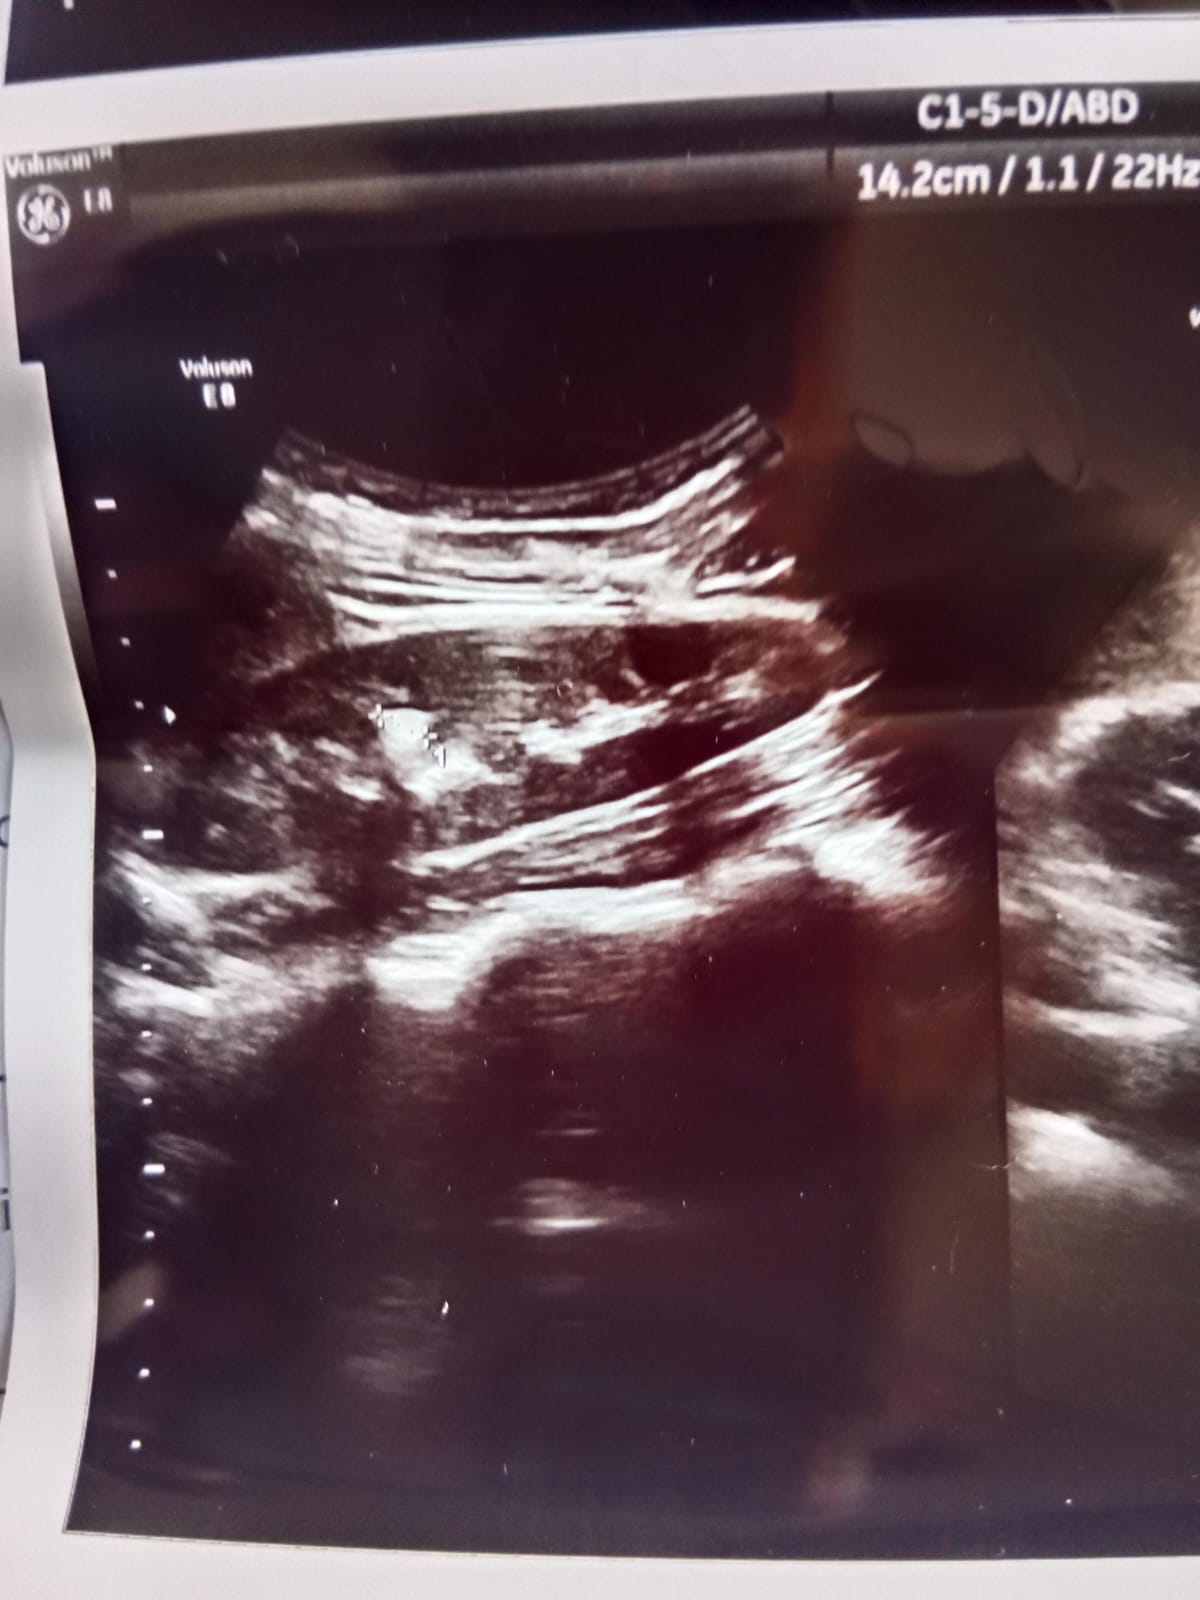

AssalamuAlikum Muja bar bar peshab ata ha peshab ka rang pani ki tra safed hota ha peyas be bhot lgte ha har 25 minutes bad washroom jna parta jis ki waja sy ma traveling be nae kar sakta kindly ko medicine bta dayn doctors ko be checkup krwaya h likan masla hal nae hua h Urine aur sugar test be krway ha vo be normal h Right kidney ma 7.5 mm ka stone h Ma bhot zyda preshan hu Kindly help kr dy kon c medicine lu Mare age 23 ha

excellent ultrasound pictures

detailed evaluation needed bro